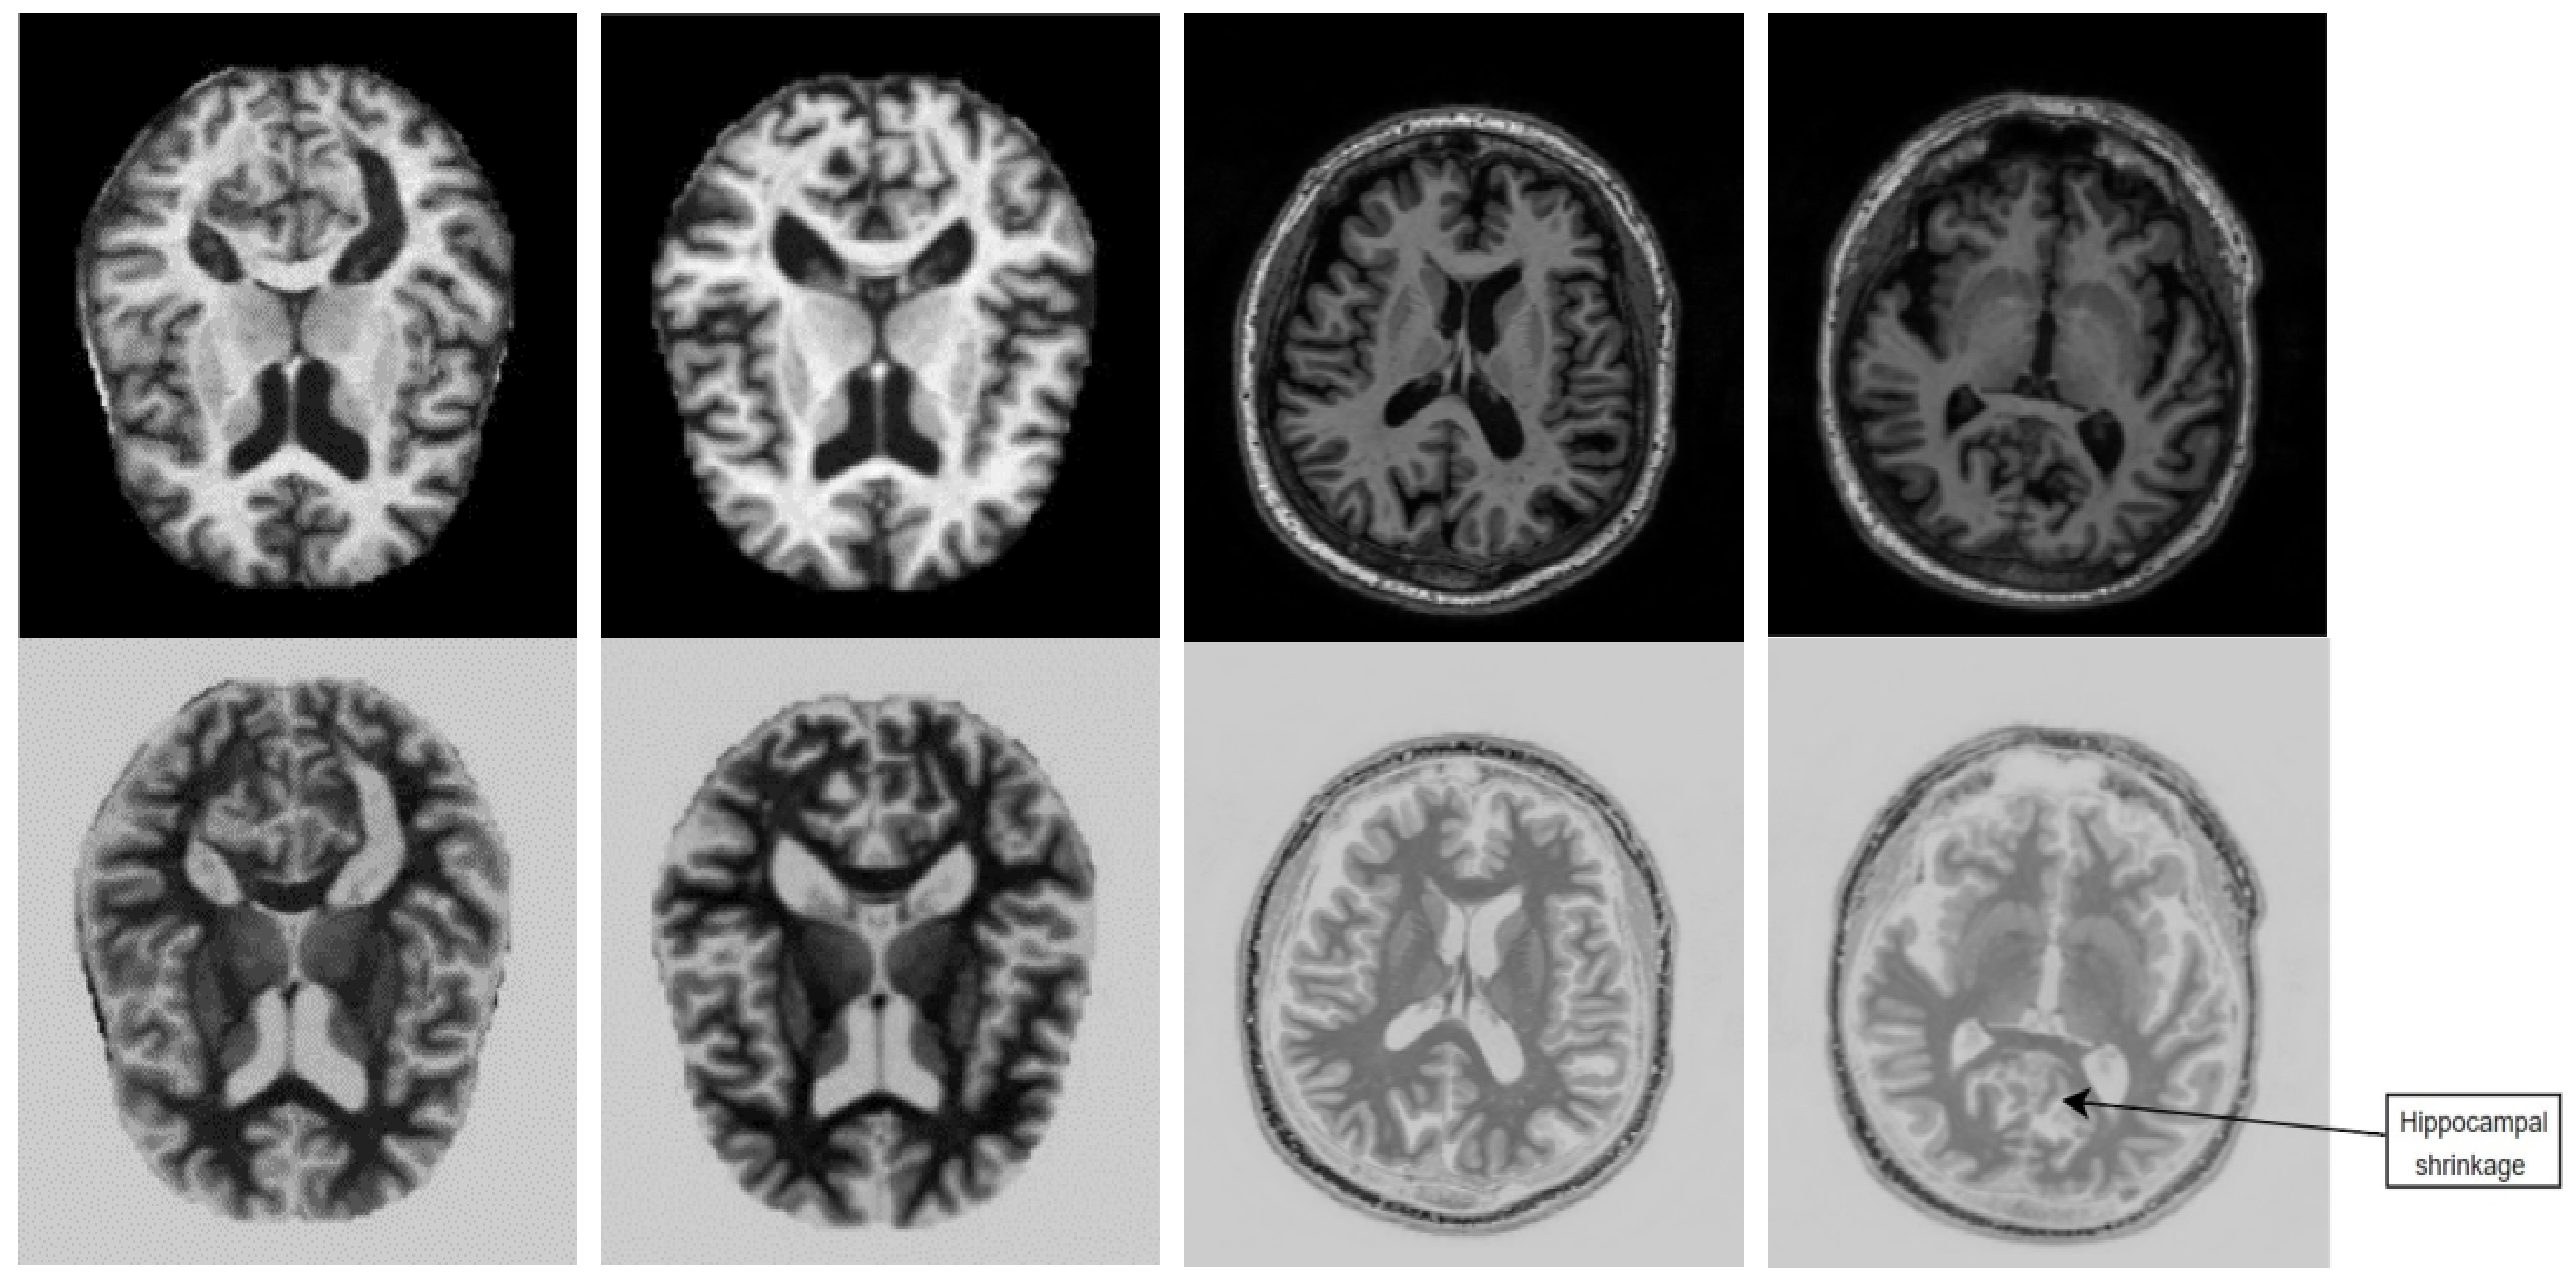

Figure 2: First row represents the original MRI images, 2nd row represents the images after passing it through Tx-layer

The parallel concatenation block (pcb) is one of the novelties of our research, shown in Fig.1. This pcb starts from a transformation layer (tx-layer), output of this tx-layer Io(f)subscript𝐼𝑜𝑓I_{o}(f) is given in equation (5). This tx-layer is followed another 2 convolutional layers and two Max-Pooling layers, as shown in Fig.1.

Io(f)wxw=m(255I(f)w×w)subscript𝐼𝑜subscript𝑓𝑤𝑥𝑤𝑚255𝐼subscript𝑓𝑤𝑤I_{o}(f)_{wxw}=m*(255-{I(f)}_{w\times w}) (5)

where, Io(f)subscript𝐼𝑜𝑓I_{o}(f) is the output of that transformation layer, I(f)𝐼𝑓I(f) is the input tensor coming to the transformation layer, m𝑚m here is a real constant whose value is supposed to be 0<m<10𝑚10<m<1, empirically we have chosen the value of m=0.8𝑚0.8m=0.8 in this research. The purpose of this layer is to present the MRI images in such a format that it can highlight some hidden features which was not so prominent previously in the input tensor. In other words, it converts the original images into its negative version, such that it can extract additional essential features for Alzheimer’s detection. We have further ensured that with medical hospital doctors. For instance, this is evident from Fig.2 (first two images) that the gray matter substance in hippocampus’s anatomy [3] of the original MRI image is more prominent after passing it through this Tx-layer. Similarly, in the last two images, in Fig.2 it has been highlighted that hippocampus shrinking [4] is more clear in the 2ndsuperscript2𝑛𝑑2^{nd} row. Moreover, abnormal levels of beta-amyloid [4] and widespread deposits of this protein becomes more visible after passing the MRI images through this Tx-layer, according to the neurologists. These are significant features of AD that get more highlighted after utilizing the Tx-layer.

The significance of Tx-layer in pcb, is explained in the following:

It can be observed from Fig.2 that the regions in the original image which were white, become more prominent and clear after passing through the Tx-layer. In contrast, areas in the transformed images that have changed to white (previously it was black in the original) become less prominent. Hence, it can be concluded that these two pairs of images (original and Tx-layer images) possess kind of complementary features. After consulting with neurologists, we came to know that this complementary features also carry some important information for AD detection. Therefore, incorporating both combinations of these features, enables the CNN model to learn more distinct and essential feature maps (for AD detection) than previous.

Moreover, it is evident from Fig.2 that the overall statistics in the original image and the processed image (i.e., after passing it through Tx-layer), differ significantly, thus, pcb may work like an efficient data augmenter inside the model. According to the research in [29], an efficient data-augmenter must generate synthetic images which have slightly different statistics compared to original images, otherwise, it induces overfitting in the model performance.